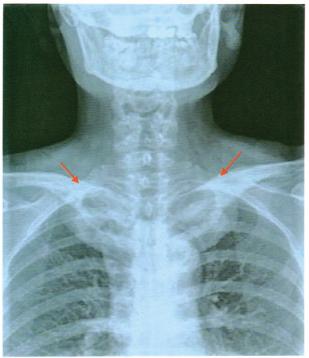

病例2就诊时胸锁关节x线显示双侧锁骨中近段明显增粗,密度增高